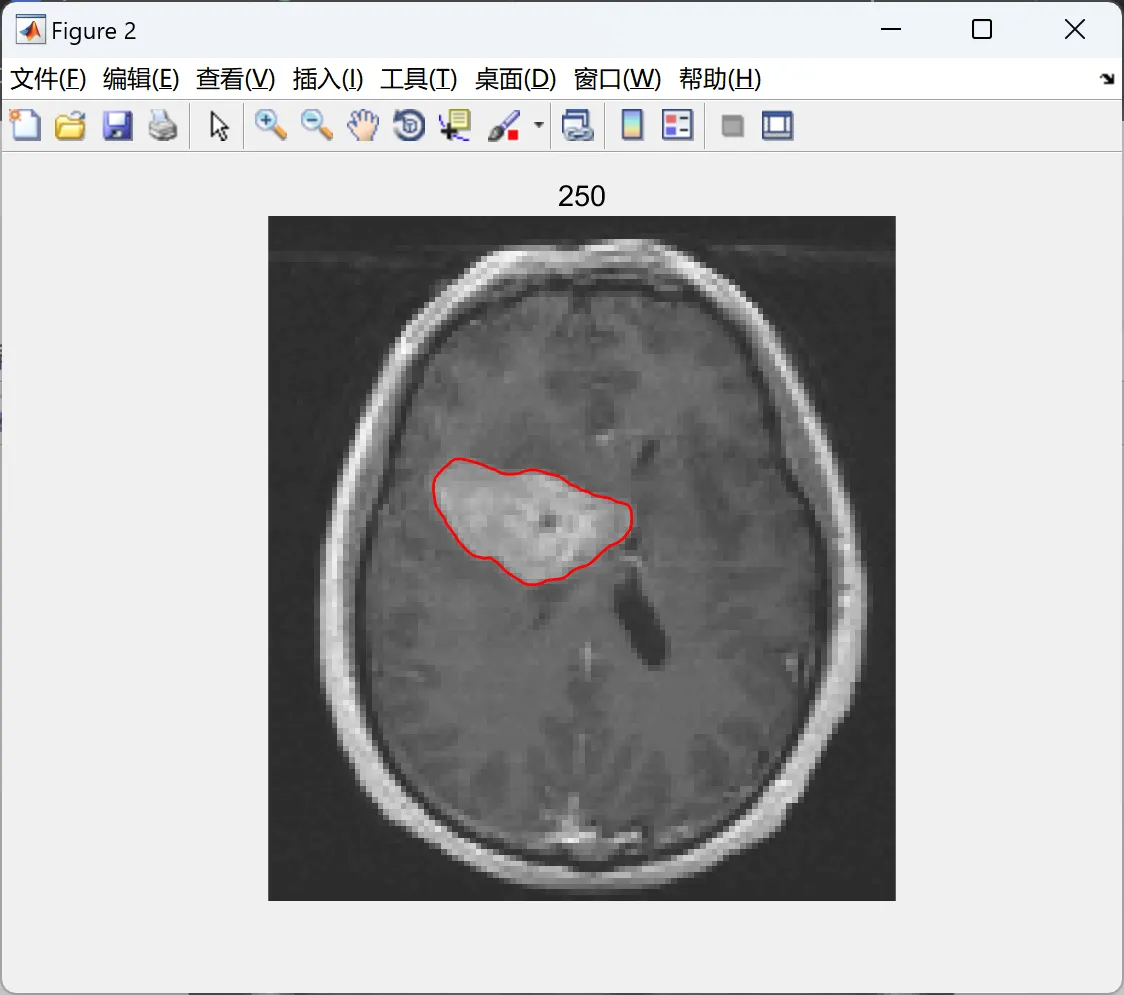

• 抗灰度不均匀性:成功分割脑MR图像中强度渐变的灰质/白质。

• 医学影像

• 肝脏CT肿瘤分割:通过局部方差差异定位病灶。

• 脑MR多组织分割:扩展多相LGDF模型划分灰质、白质、脑脊液。

📚2 运行结果

2.2 测试2

image.gif 编辑

NumIter = 250; %iterations